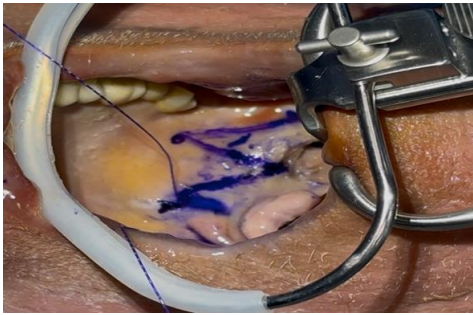

One needle was introduced at the center point then passed laterally within the palate, turning around pterygomandibular raphe till it comes out at the most superior part of the raphe at one side, the thread is pulled until it hangs at the central transition zone which is a free zone present between the two directions of the thread. The needle again is re-introduced close to point of exit, passing around the pterygomandibular raphe, till it comes out into the tonsillectomy bed, then through the upper part of the palatopharyngeus muscle and comes out near to mucosa of posterior pillar not through it. The posterior pillar is entered at the junction between the upper third and the lower two-thirds. Then, again the needle is passed back through the tonsillectomy bed and then this suture will be suspended around the raphe again, a gentle traction is then applied on the thread only and no knots are taken.

This leads to a stable repositioning of the posterior pillar to more lateral and anterior location without any knot, then this stitch is repeated at least three times between raphe and muscle till the lower pole of the muscle is reached. The opposite side is done by the same way. Finally, cach thread comes out at the raphe of the same side, for locking of the stitches and looseness prevention; a superficial stitch in the opposite direction is taken, and then the thread is cut while bushing the tissue downward for more traction

Figure 1